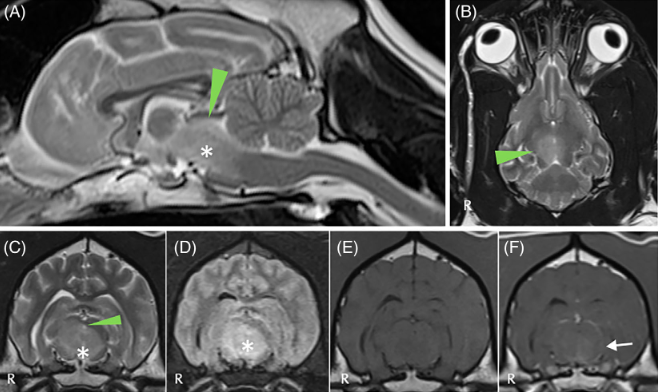

전뇌의 이상 즉, 뇌의 질병에 의해서도 이를 갈 수 있다는것을 보여주는 증례가 보고되었다.

MRI 까지 촬영하여 진단한 증례만을 보고하는것이기에 진단되지 않은 환자는 더 많을 수도 있다는것을 의미한다.